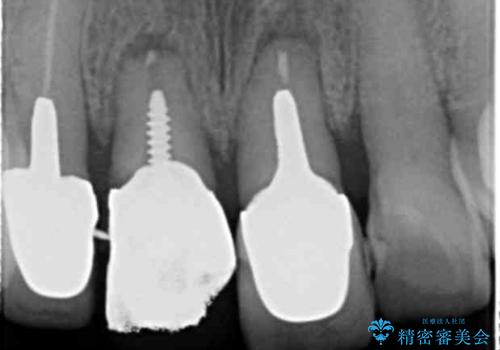

3. ぐらつく前歯 ブリッジ治療の治療後